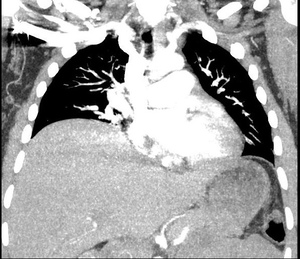

Chest CT showed large right pleural effusion consistent with a hemothorax and possible pulmonary embolism of distal vessels which was thought to be secondary to artifact after discussion with radiology. (Figure 1 and 2). Abdominal/pelvic CT showed significant heterogeneous intrauterine material and findings consistent with post-op c-section.

The patient had a steadily declining Hemoglobin/Hematocrit (H/H) of 10.9/33.4 preoperatively to 6.9/20.7 on evening of postoperative day 2. She was given a 2nd unit PRBC with improvement of her H/H to 8/23. Pt clinically had very minimal vaginal bleeding since surgery and her uterus was noted to be firm at the umbilicus. There was some concern for slow uterine hemorrhage, but the patient was deemed a poor candidate for anesthesia given large pleural effusion in the case of operating room take back. General surgery was consulted who recommended thoracentesis later that day by Interventional Radiology which was performed without issue and notable for drainage of 675 mL of dark bloody fluid. Post-thoracentesis the pt noted some improvement of her shortness of breath but still reported significant chest pain and shortness of breath. We reordered a CT to re-evaluate for clot which was negative however repeat CT showed a significant improvement in fluid present in her right lung (Figure 3).